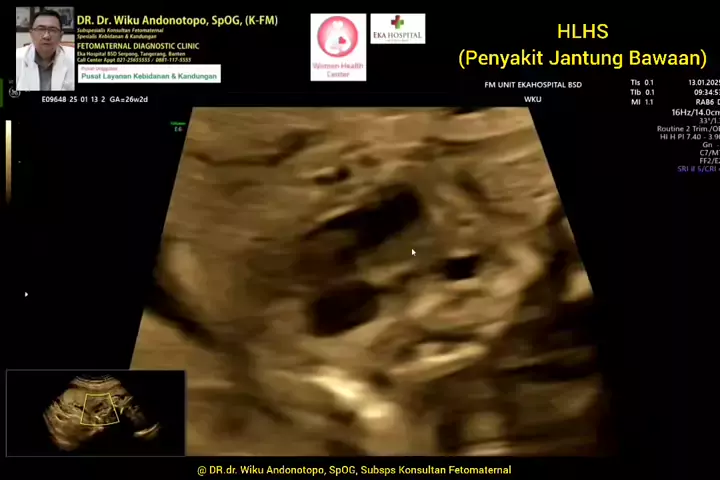

Hypoplastic Left Heart (HLHS) penyakit jantung bawaan.. #skriningkehamilan #drwikuandonotopo #drwiku_andonotopo #polikandunganekahospitalbsd #ekahospitalbsd #ekahospitalcibubur #ekahospitalpekanbaru #ekahospitalbekasi #rsiafamilypluit #grandfamilypik #usgkehamilansehat #usgkehamilan #usg4d #usg4dimensi #fetomaternal #usgfetomaternal #konsultanfetomaternal #fetomaternalpontianak #fetomaternalekahospitalbsd #fetomaternaljakarta #fetomaternalserpong #fetomaternaltangerang #fetomaternalmedan #fetom...